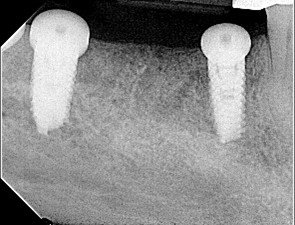

After a thorough dental and medical evaluation, including a complete set of x-rays and CBCT, a plan was developed for him. This included the removal of all broken and infected teeth, rebuilding the lower anterior teeth to improve his anterior occlusion, restoring the teeth that could be saved, and placing implants in the future edentulous sites of the lower arch. You can see on the x-rays and CBCT these areas.

At the eighth-month appointment, implants were placed in the #19, 20, 29, and 31 sites because the bone filled in nicely. Insertion torque was over 40 NCM for all implants. Healing screws were placed, and then we waited for osseointegration of the implants.

In the twelfth-month appointment, another CBCT was taken to evaluate the bone over implant #20. It can be seen on the CBCT image that there was a significant improvement in the thickness of the bone.